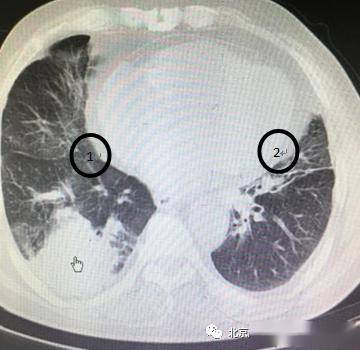

肺部有阴影是什么原因,肺部有阴影CT

又一个病例讨论-咳嗽,黄痰,肺部阴影

肺部阴影引猜测,谁是谁非谁惹祸?

肺部有阴影CT

肺部阴影诊断

肺部阴影有几种可能

肺部阴影

肺部阴影图片